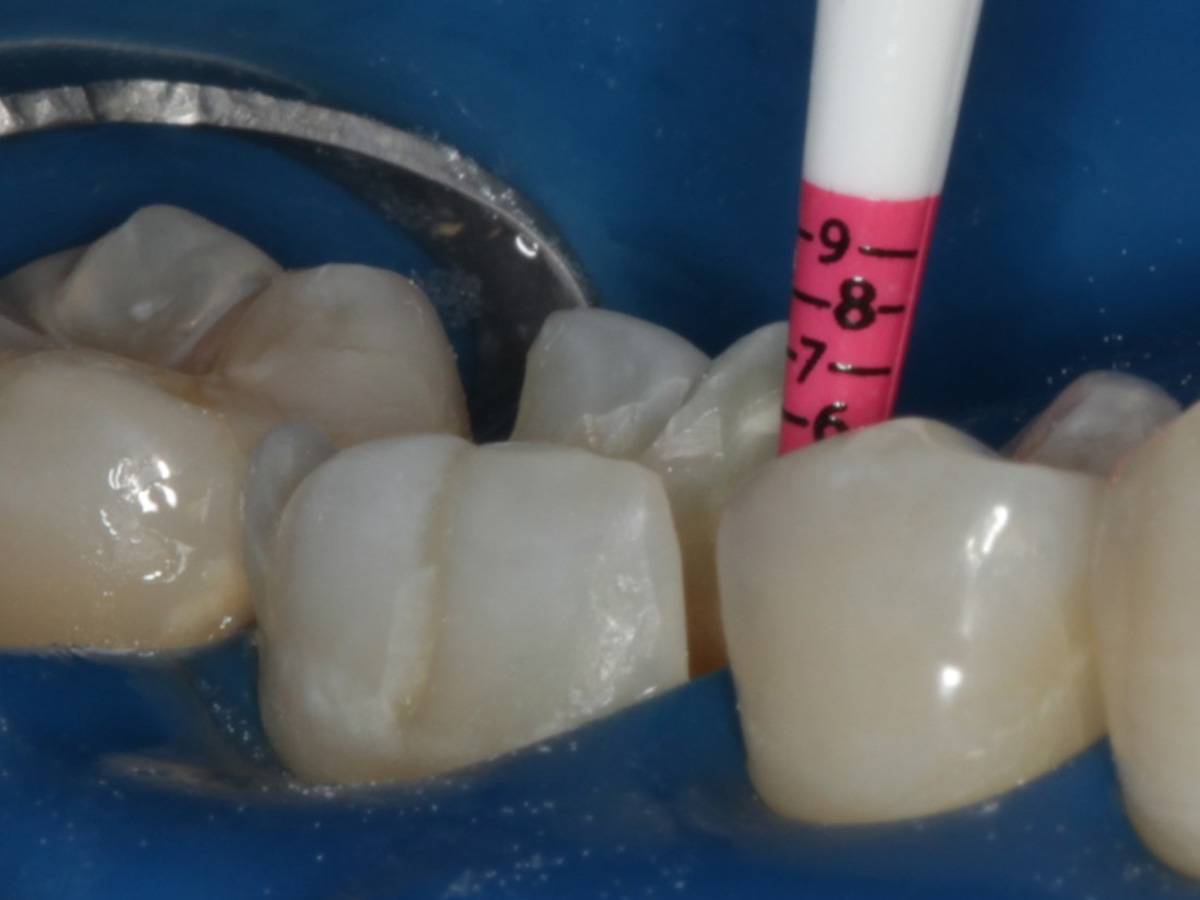

Abbildung 1

Intakte Kaufläche bei Approximalraumkaries an Zahn 36 mesial und distal

Height Indicator vor Auswahl der passenden Evolve Matrize distal

Abbildung 11

Height Indicator vor Auswahl der passenden Evolve Matrize mesial